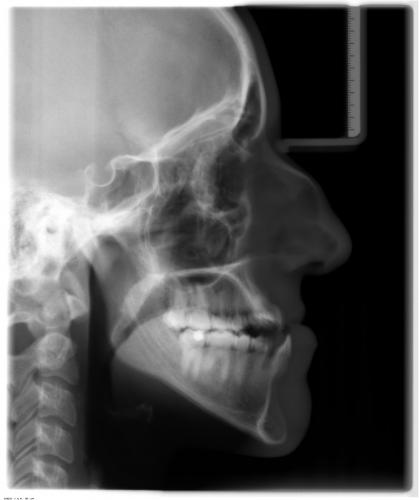

Röntgenbefund

Zu Behandlungsbeginn und nach der Operation

Die Verlagerung der Kieferbasen, v.a. im Unterkiefer, ist deutlich zu erkennen. Ferner sieht man auf dem rechten Bild die Metallplatten aus Titan, die die Knochenfragmente während der Heilungsphase in der gewünschten Position zusammenhalten. So wird frühzeitig sichergestellt, daß der Patient wieder normal kauen kann. Die Metallplatten können nach ca. 6 Monaten in einem Zweiteingriff entfernt werden.